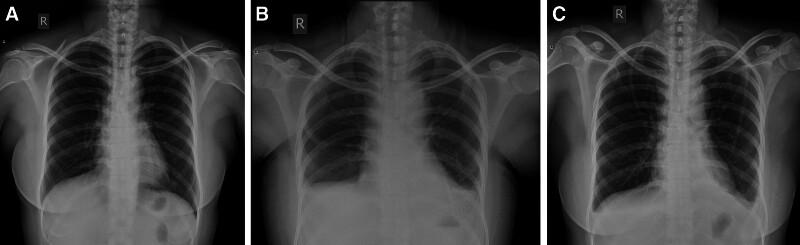

We report 2 East Asian women who developed bilateral chylothorax after undergoing total thyroidectomy with neck lymph node dissection. Both patients presented with dyspnea and significant pleural effusion postoperatively.

Both patients were diagnosed with bilateral chylothorax based on clinical examination and imaging studies, including chest ultrasonography and X-rays.

根据临床检查和影像学研究,包括胸部超声和 X 线,均诊断为双侧乳糜胸。